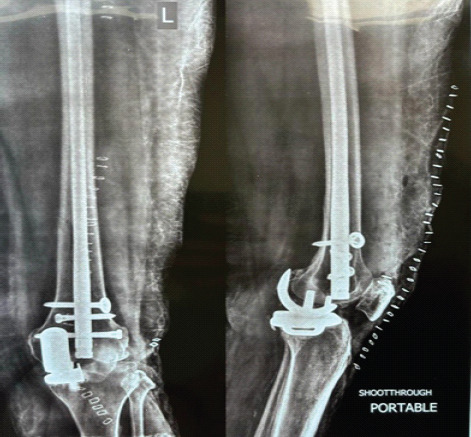

Case report: We present two unique cases of PPFs following cemented mobile-bearing Oxford UKA in elderly South Asian women. The first case involves a 63-year-old woman who sustained a high-energy supracondylar femoral PPF (Unified Classification System Type C) 9 months post-UKA. Despite the severity of the injury, radiographs confirmed the femoral component remained well-fixed with no evidence of polyethylene insert dislocation. She was treated successfully with retrograde intramedullary nailing, achieving full fracture union and 130° of knee flexion by 6 months postoperatively. The second case involves a 60-year-old woman who sustained a proximal third tibial PPF (Type C) two and a half months after UKA. Again, both components remained secure without signs of loosening. She was treated with locking plate fixation, resulting in complete union and full independent ambulation by 6 months. Both patients remained clinically well at 2.5 years of follow-up, with intact UKA components and no functional limitations.